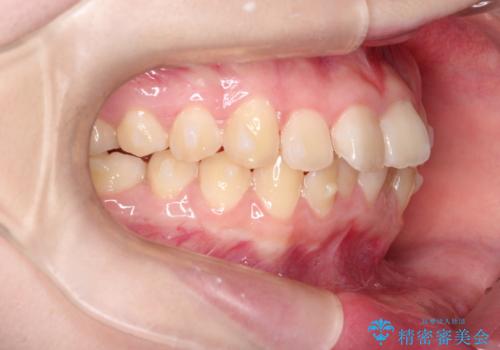

なるべく通院回数を減らして矯正したい インビザラインでのガタガタ矯正

- 10代女性

- インビザライン

- 1年2ヶ月

- 上下の歯並びを治したいとのことで来院されました。

受験生ということもあり、なるべく通院回数を減らしての矯正を希望されたので、インビザラインで治療をすることにしました。

ワイヤー矯正が1か月に1回程度来院が必要なのと比較すると、2-3か月に1回の来院でもよいので(症例によります)、通院回数を減らすことができて、患者様の負担を減らすことができます。